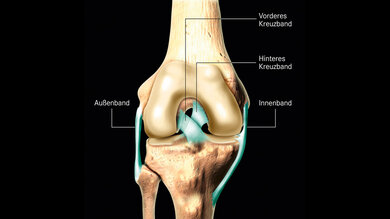

Das Knie ist ein Gelenk. Gelenke machen Körperteile beweglich. Das Knie verbindet Oberschenkel und Unterschenkel miteinander. Am Kniegelenk sind mehrere Bänder. Die Bänder halten die Knochen im Kniegelenk zusammen. Und die Bänder machen das Gelenk stabil. Das Kniegelenk wird durch diese Bänder gehalten:

- Außenband

- Innenband

- vorderes Kreuzband

- hinteres Kreuzband

Im Knie sind verschiedene Bänder. Die Bänder sind im Bild hellblau eingezeichnet.